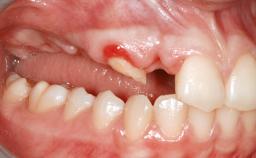

A 20-year-old woman was referred for implant therapy in 2004. Her medical history revealed no significant findings, and neither did she smoke nor take any medications. An extraoral examination revealed no abnormalities of the skin, hair or nails. The intraoral examination revealed only 11 permanent teeth clinically. These were normal in shape, size, and color. In addition, eight retained deciduous teeth (53, 62, 63, 71, 72, 73, 81, 82) were present. No abnormalities were detected during the general examination. The family history revealed that the patient’s father and two sisters were on record with similar conditions. The clinical examination revealed a thick gingival biotype. No recession of the attached gingiva was noted, but the retained deciduous teeth were mobile and unsightly. As a syndrome had not been diagnosed, the case was categorized as non-syndromic oligodontia.